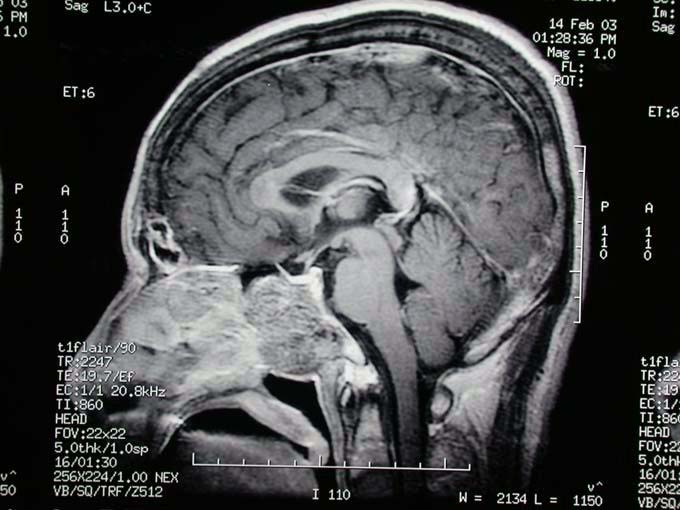

术前